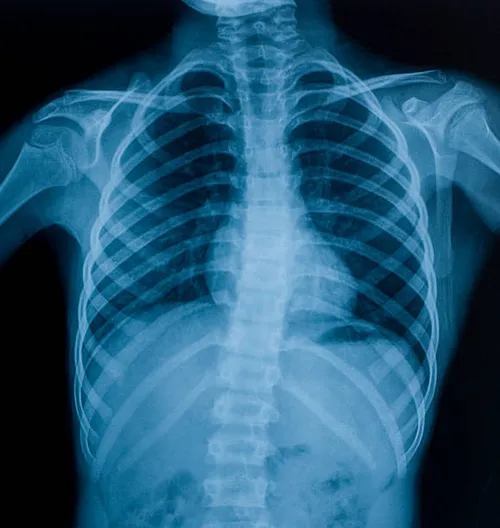

At Pulse Clinic, we are dedicated to providing comprehensive healthcare services that meet the diverse needs of our patients. With a team of highly skilled professionals and cutting-edge technology, we offer a wide range of medical services and diagnostic facilities to ensure your well-being. Here's an overview of the services we provide: